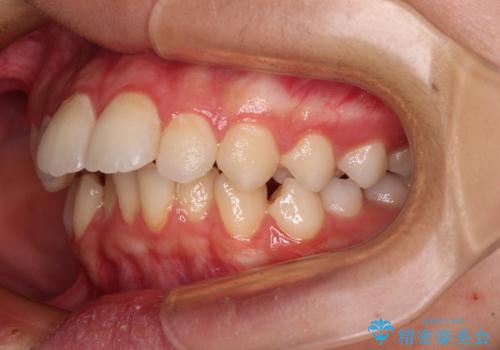

- 上顎前歯の突出感を気にして来院された患者様です。

舌の突出癖などにより、上下前歯の間に指が入るくらい隙間のできる状態でした。

下顎は叢生があったため、上下左右の第一小臼歯4本を抜歯し、更には口元の突出感を大きく改善させるために、上顎臼歯を後方に移動させるための補助装置をしようし、ワイヤー装置にて矯正治療を行うこととしました。